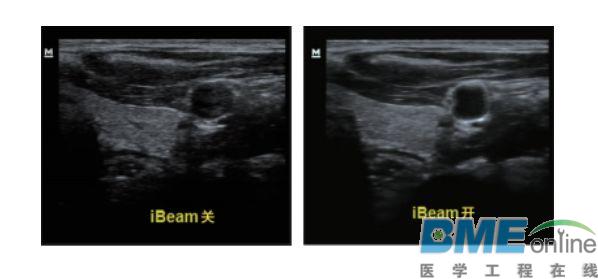

设备型号DP-50 全自动便携式超声诊断系统(迈瑞),该设备为DP 系列超声的较高级版本,具有iTouch 图像一键优化、 iBeam 复合成像、iClear 斑点噪声抑制、宽带频移谐波等技术。

iBeam复合成像: